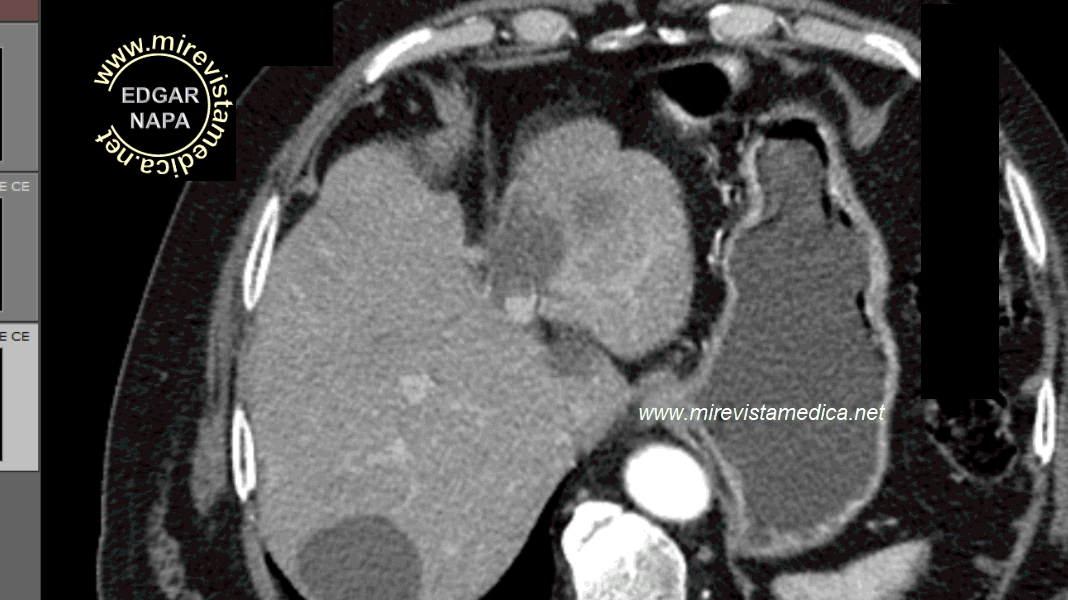

Tomografía abdominal, sin contraste, muestra imagen hiperdensa en la fosa vesicular. en relación con vesícula de paredes calcificadas.

Tomografía abdominal, sin contraste, muestra la pared hiperdensa que delimita su silueta.